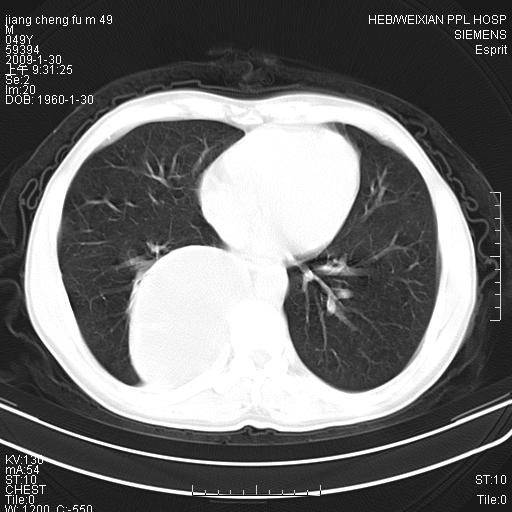

男性,49岁,主因胸痛,右肺呼吸音低。胸片提示肺占位

考虑右侧脊柱旁沟囊性病变。1:支气管囊肿或食管囊;2:神经源性肿瘤。

右后纵隔囊性占位;考虑为:1)淋巴管囊肿。2)食管囊肿。建议:进一步检查。

右后纵隔囊性占位,建议先做增强,后做穿刺活检。

在分析这个病变时,首先病灶边界清晰,但其内密度不均匀,有条索状状实性成分,肿块的外侧壁亦呈一不均匀的厚壁改变,因此支气管囊肿的可能性不大。主要考虑神经源性肿瘤(主要考虑神经鞘瘤,因为它囊变的机率比较高),其次考虑肺膈离征,行增强扫描如发现来自胸主动脉供血动脉血管可确诊。

考虑右侧脊柱旁沟囊性病变,囊骨有分隔,囊壁较厚。1:神经源性肿瘤;2:食管囊肿或淋巴管囊肿。支持!

囊状肿块内有线样软组织分隔,支气管囊肿及食管囊肿可不考虑。我考虑:1、囊性肺膈离征(需要增强扫描来排除)。2、神经鞘瘤。3、淋巴管囊肿。